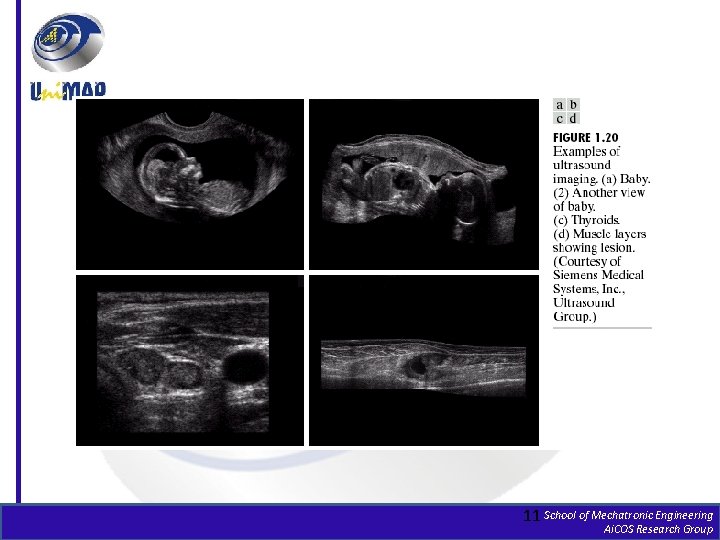

Medical Images Chromosomes Brain MRI 10 School of Mechatronic Engineering Ai. COS Research Group

11 School of Mechatronic Engineering Ai. COS Research Group